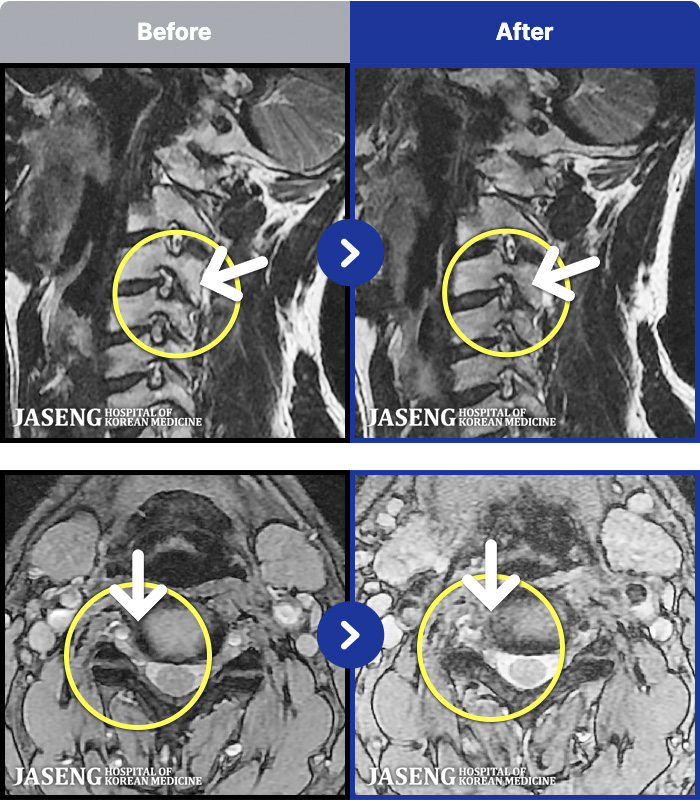

54 MRI ũ ʸ Ȯϼ.

ȯںп Ǹ ǿ ԿǾ, ο ġ ۿ Ƿ ġḦ Ͻñ ٶϴ.